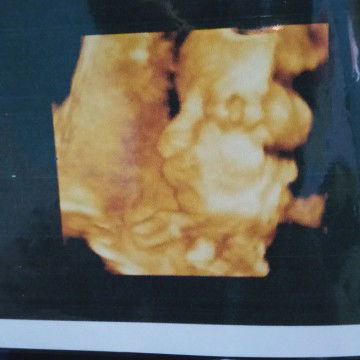

durian

Bun boleh ga sih hamil 35w makan durian?